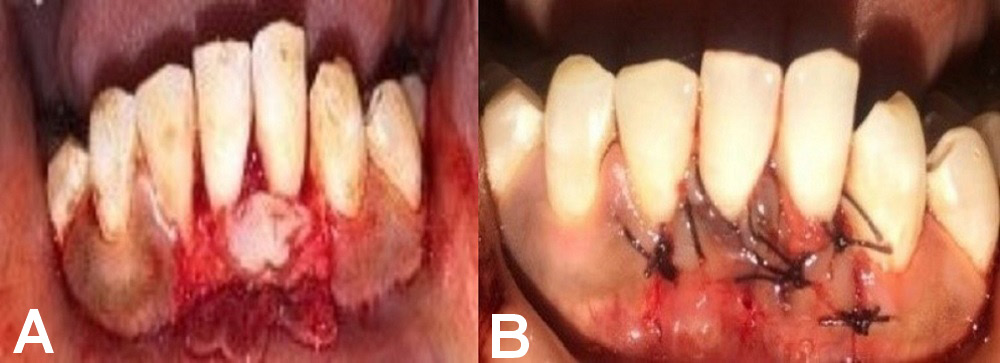

Group A comprised 12 patients who underwent surgery to treat their denuded roots by CAF and PRF application (Figure 2).

Group A

A full-thickness submarginal trapezoidal flap was raised with the use of blade No. 15 on the labial aspect of the tooth being treated, through an intrasulcular incision extending horizontally to dissect the labial aspect of the adjacent papilla. Two vertical incisions were made – one at the distal gingival line angle, and the other at the mesial line angle of the subject’s affected tooth. The submarginal horizontal incisions connected with the vertical incisions were extended up to the mucogingival junction (MGJ) to provide the proper displacement of the flap. The flap was raised through sharp dissection. The papillae were de-epithelialized. Before placing the pedicle flap on the denuded root, thorough root planing was performed using curettes, and the prepared PRF membrane was placed and sutured using 4–0 resorbable sutures. The pedicle flap was then sutured 1 mm coronal to the cementoenamel junction (CEJ) of the affected tooth, using 4–0 resorbable sutures. A COE-PACK™ dressing was applied (Figure 4).